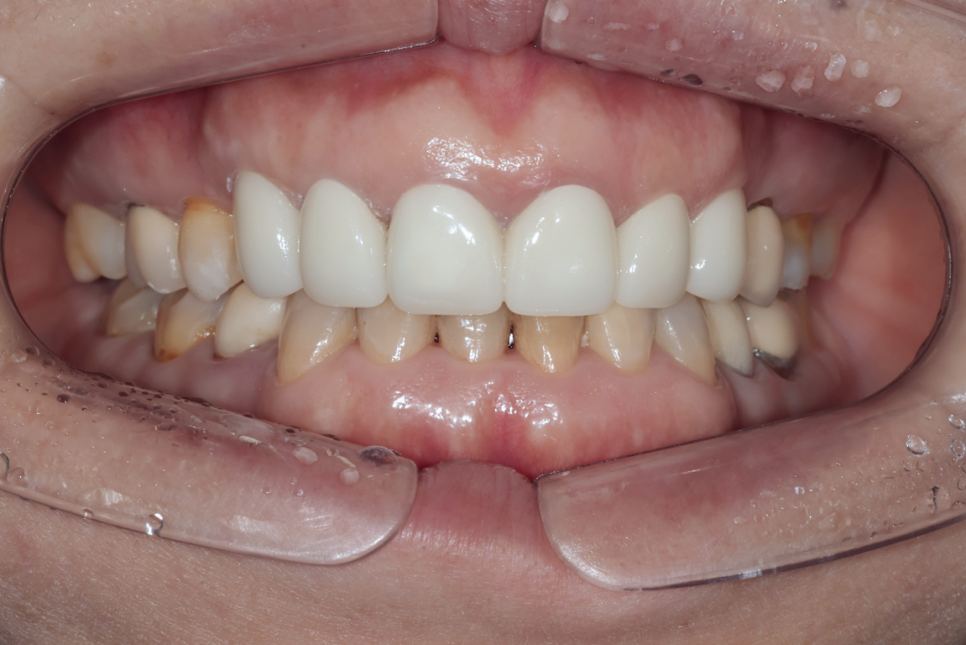

최종 결과 – 자연스럽고 조화로운 앞니 완성

최종 보철 완성 – 모든 치아가 자연스럽게 정리된 모습. 가운데 두 앞니는 연결 크라운으로 제작했습니다

약 3개월간의 임시 크라운 기간을 거친 후, 환자분이 다시 한국에 방문하셨을 때 최종 PFZ 크라운 6개를 세팅했습니다.

치료 전후를 비교하면 다음과 같은 개선이 이루어졌습니다.

| 치료 전 | 치료 후 |

|---|---|

| 치아 사이 검은 삼각형 공간(블랙트라이앵글) | 블랙트라이앵글 대폭 개선 |

| 앞니 사이 벌어진 공간 | 공간 해소, 가지런한 배열 |

| 크라운 변색, 색상 부조화 | 자연스럽고 균일한 색조 |

| 크라운 마진 부적합 | 정밀한 마진 적합 |

| 앞니 사이 다시 벌어질 위험 | 연결 크라운으로 재벌어짐 방지 |

| 입술 돌출 우려 | 평탄한 크라운 윤곽으로 입술 라인 개선 |

아랫니와도 자연스러운 조화를 이루는 모습